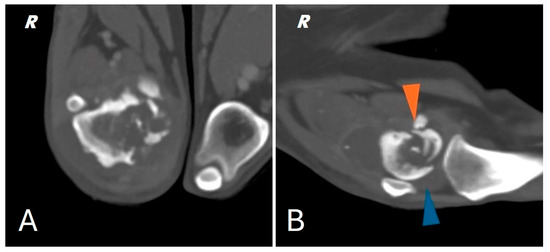

Radiographs of the right hind limb were taken in mediolateral and craniocaudal projections under sedation and analgesia (Figure 1).

The radiograph showed evidence of osteoarthritis of the right hip joint with bone remodeling of the femoral head and neck. Significant structural changes were observed in the distal metaphysis of the right femur, with a marked “moth-eaten” pattern of bone lysis, pronounced and irregular periosteal reaction and extensive alteration of the normal pattern of the medullary canal in a disto-proximal direction up to the level of the middle third of the diaphysis. A complete, comminuted, slightly dislocated pathological joint fracture of the medial femoral condyle, osteoarthritis of the distal pole of the patella and marked joint and periarticular soft tissue swelling of the femorotibial–patellar joint were also found. Finally, there was moderate sclerosis and mild osteophytosis of the tibiotarsal joint.

Figure 1. Different radiographic projections of the right hind limb. (A) mediolateral projection of the tibia, (B) mediolateral projection of the femur, (C) cranio-caudal projection of the femur. Structural and radiopacity alteration near the distal femoral end and the knee joint is repeated in all projections performed.